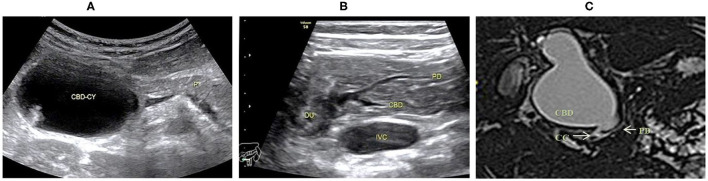

On the basis of the new JSPBM’s classification, the individual morphologic features of PBM were described as four types (ref. 11) in presenting our ultrasound report: type A (stenotic)—the distal CBD with stenosis before joining with the CC, and an angle of slightly < 90° usually observed in the conjunction between PD and CBD at a site distant from the papilla of Vater; type B (non-stenotic)—the distal CBD emerging but without stenosis pattern before joining with the CC, in addition, an approximately right angle customarily seen in the conjunction between PD and CBD at a site distant from the papilla; type C (dilated channel)—the dilated CC significantly occurred; type D (complex)—a complicated configuration in PBJ contexture including the PD, the terminal portion of the CBD, and the dilated accessory PD, and one end opening as a small nipple in the duodenum and the other end converged with the CBD downward into the CC. Figures 1–4 show the representative imagines of A, B, C, and D types of PBM, respectively.

Among the 31 cases, 14 cases were stenotic type (A), 11 cased were non-stenotic (B), and five were dilated channel (C). The complex type (D) rarely occurred and only one case was found in our medical center. Table 3 shows the comparison among A, B, and C types in terms of gender, age, the maximum internal diameter of CBD, the internal diameter of CC, the length of CC, the internal diameter of the main PD, and the thickness of the gallbladder. Type A causes a significant increase in the internal diameter of CBD. Type C appears significant increases in internal diameter and length of CC and internal diameter of PD.